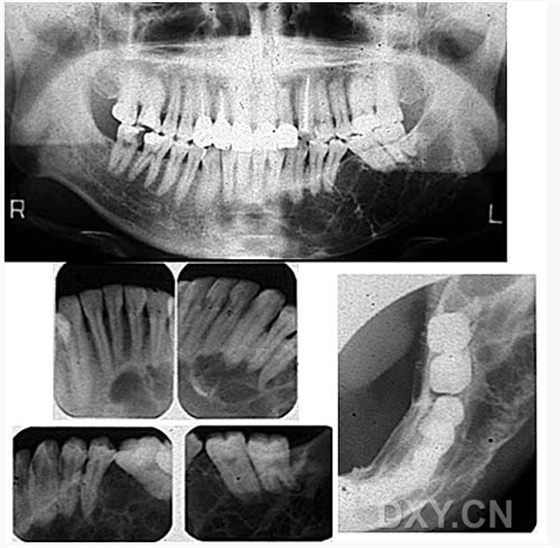

成釉細胞瘤

根尖囊腫

含牙囊腫

球狀上頜囊腫    含牙囊腫